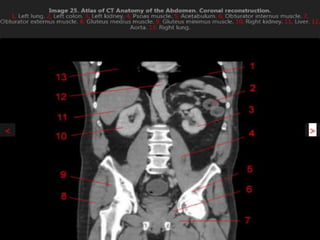

CT cross sectional anatomy.

MRI anatomy images of the abdomen.